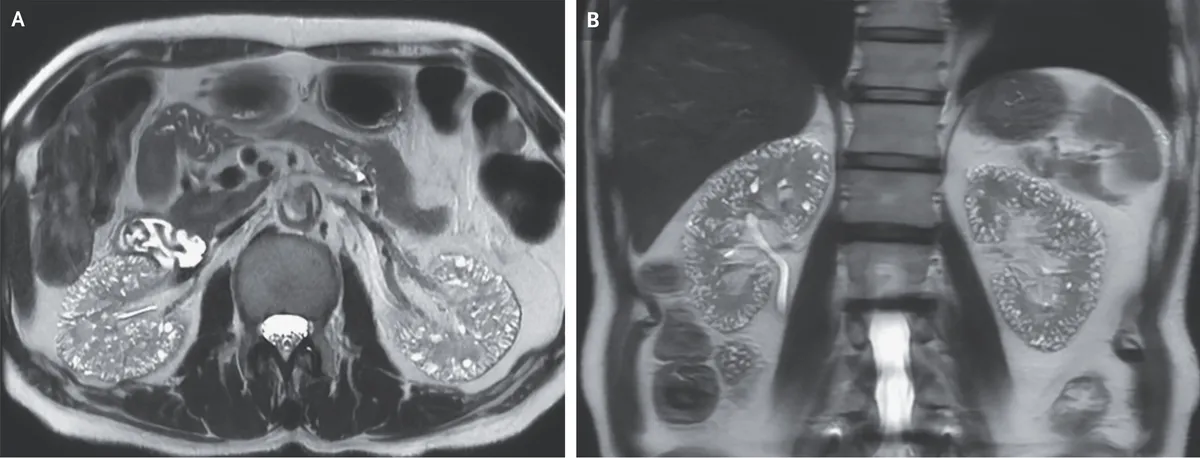

Homem de 60 anos, com histórico de hipertensão arterial e transtorno bipolar, foi submetido a uma ressonância magnética (RM) abdominal para investigação de sintomas do trato urinário inferior.

De forma incidental, foram observados pequenos cistos renais. O paciente havia utilizado lítio por 17 anos como estabilizador do humor, tendo suspendido o medicamento há 1 ano devido à deterioração da função renal (aumento da creatinina sérica para 1,8 mg/dL)

O paciente negava qualquer histórico familiar de doença renal cística. A RM ponderada em T2 revelou numerosas microcistos localizados no córtex e na medula de ambos os rins (Imagem abaixo - Painel A, corte axial; Painel B, corte coronal).

Foi feito o diagnóstico de microcistos compatíveis com nefropatia induzida por lítio. O uso de lítio está associado a diversos efeitos nefrotóxicos, incluindo diabetes insipidus nefrogênico, acidose tubular renal e nefropatia túbulo-intersticial crônica.

Microcistos de 1 a 2 mm podem ser observados em exames de imagem em pacientes com nefropatia túbulo-intersticial crônica induzida por lítio. O paciente permaneceu em tratamento com agentes alternativos para o transtorno bipolar. Após 2 anos de seguimento, a função renal manteve-se estável.